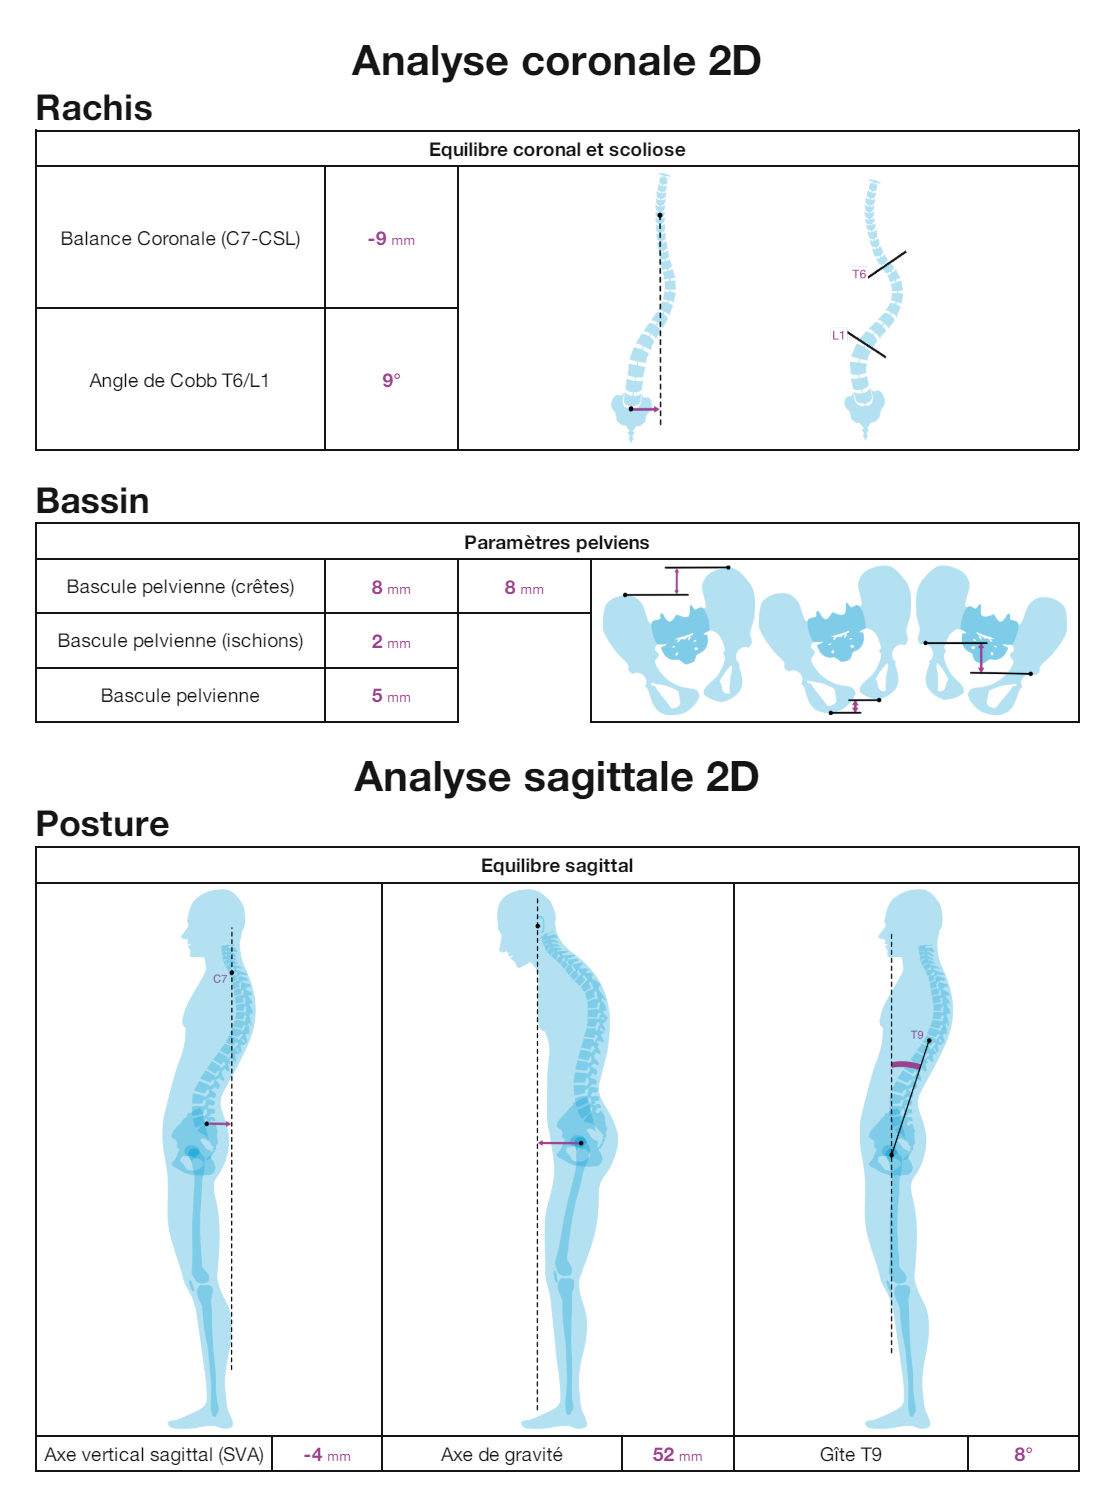

EOS-compatible measurements, with analysis report

TechCare Spine addresses the unique challenge of spinal medical imaging. The spine has significant anatomical complexity, and its central role in body posture and mobility must be leveraged by the latest deep learning advancements. This is why we provide radiologists and orthopedic surgeons with TechCare Spine, a tool for automatic measurements adapted to EOS imaging, offering significant time and productivity savings.

PELVIS : Pelvic version | Pelvic incidence | Sacral slope

SPINE : Coronal balance (CVA) | Sagittal balance (SVA) | Cyphosis T1-T12 | Heel T9 | Lordosis L1/S2 | Cobb angle | Gravity axis

ANALYSIS REPORT